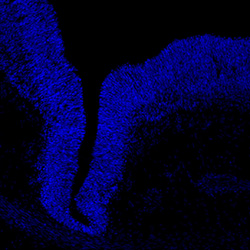

DAPI

6PCW human midbrain